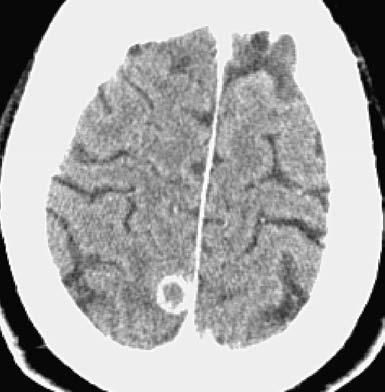

Figure 4 – Ring-enhancing lesions in the right cerebral hemisphere are revealed in this CT scan of the patient's head.

The patient was referred to otolaryngology for a biopsy of the mouth ulcers. The pathology of the left arytenoid and anterior subglottic region revealed ulcers with acute and chronic inflammation, reactive atypia, and yeast-like organisms. After the patient was referred to the oncology clinic with the presumptive diagnosis of metastatic cancer, CT scans revealed numerous small ring-enhancing cortical brain lesions (Figure 4) and a left main-stem endobronchial mass (Figure 5).